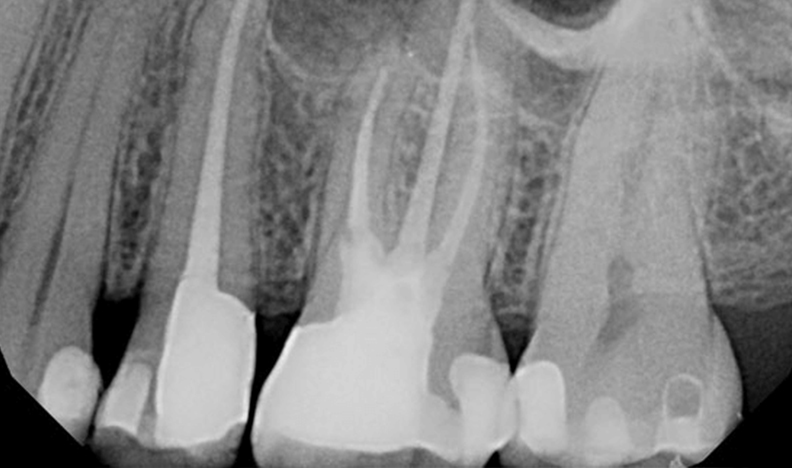

Final canal instrumentation:

25: WL = 24mm instrumented to 35/0.04

26: MB1: 19mm to 35/0.04 MB2: 19mm to 35/0.04 DB: 19mm to 35/0.04 P: 22mm to #40 SS file

Both teeth irrigated with NaOCl(aq) and 17% EDTA (aq) with Piezoelectric ultrasonic activation, obturated with gutta percha and Kerr RCS via System B downpack and Obtura backfill. Final fillings were completed with Air abrasion/phosphoric acid etch/Kerr Optibond FL/Ultradent Permaflo Purple on orifices/Dentsply Esthet-X flowable A1/Esthet-X A3. Treatment complete under Global Surgical Operating Microscope.